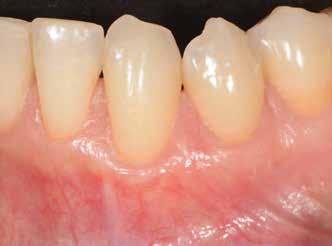

12. b. ábra: Okkluzális nézet négy hónappal a műtét után, amely megfelelő bukkális lágyszövetvastagságot mutat.

13. ábra: Négy hónap elteltével a szájüregben látható marginális zenit megmaradt.

14. ábra: Egészséges implantátum körüli lágyrészgallér.

uni.fit titánalapra (bredent medical). Az implantátum körül a bukkális lágyszövet megfelelő vastagságot és kedvező ínykontúrt mutatott (12. a–b. ábra). Az egyedi ínyformázó eltávolítása után egészséges implantátum körüli lágyrészgallér

értünk el (19. ábra). Az okkluzális nyílást tefloncsíkkal és kompozittal zártuk (20. ábra). Mindezek után, posztoperatív kontroll röntgenfelvétel készült, amely a pótlás megfelelő illeszkedését mutatta (21. ábra). A hat hónapos utánkövetés során jól megfigyelhető a teltebb lágyszöveti profil és a megtartott kresztális csontszint (22–24. ábra)